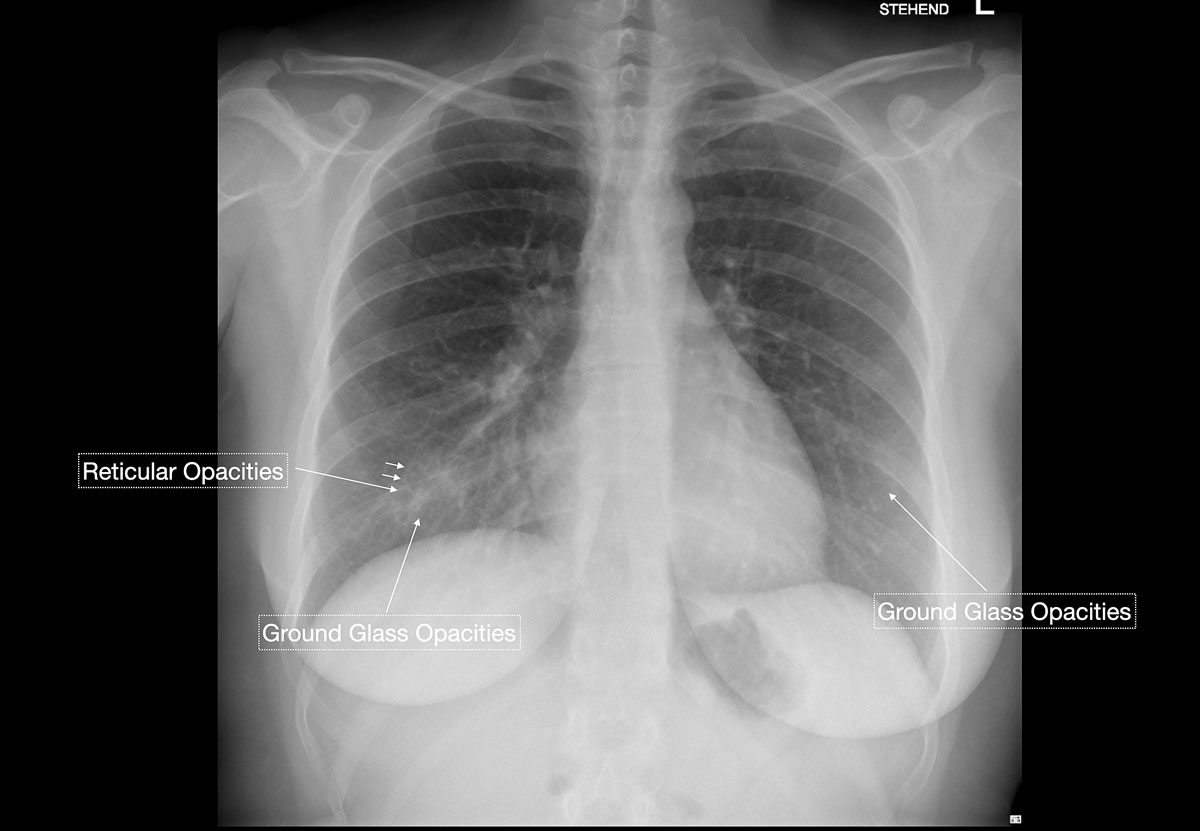

Studies [4, 13, 14] have shown that in early stages, COVID-19 and atypical, interstitial pneumonia share the same primary findings. Typically our patients presented with bilateral reticular (64%) and patchy either ground glass (64%) or consolidative air space opacities (45%), with a peripheral and basal distribution (detailed definitions of these features are illustrated in figs 1 and 2 ). Since ground glass opacities may be very subtle in appearance, their detection on a chest x-ray is sometimes uncertain. Pleural effusions are rare and were seen in only 13% of our COVID-19 patients. In later stages, features of organising pneumonia with accentuated bilateral patchy consolidations were observed (fig. 3).

Figure 1 Schematic depiction of typical chest x-ray findings for COVID-19: bilateral, reticular and focal ground glass opacities or consolidative air space opacities in a peripheral and basal distribution. Earlier stage disease shows predominantly ground glass opacities; with progression pre-existing ground glass opacities transform into consolidative air space opacities.

Figure 2 A 71-year-old male patient with cough, intermittent fever and progressive dyspnoea. Early findings were predominantly peripheral ground glass opacities and reticular opacities. No consolidations or pleural effusions are seen. Subsequent nasopharyngeal RT-PCR test was positive for COVID-19.

Figure 4 A 31-year-old female patient working as a waitress presented with episodes of high fever and progressive shortness of breath. Chest x-ray, performed at the same time as nasopharyngeal RT-PCR testing, showed very subtle evidence of faint ground glass opacities and with a superimposed reticular pattern, which raised the high suspicion of an early stage COVID-19 infection. No consolidation or pleural effusions were evident. RT-PCR test results available after 48 hours confirmed COVID-19.